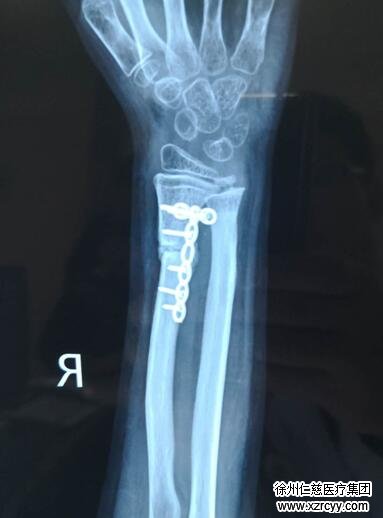

“与成年人相比,小孩骨骼未发育成熟,手术难度较成人大很多,更何况是二次修复?手术路径、角度的选择,每一个环节都要精心设计。”经过充分的术前准备,齐主任结合尺桡骨远端的生物力学特征,为冬冬量身定制了“右桡骨骨折端不愈合切开复位内固定+取髂骨植骨术”,术中清除骨折端硬化骨,打通髓腔,在孩子右侧髂骨处取骨,放置于桡骨断端处,对骨折端进行了严丝合缝的复位,经过三个多小时的手术,冬冬的右手腕骨折得到了满意的复位。齐主任表示,经过后期的康复锻炼,孩子的手部功能将有望得到全部恢复。